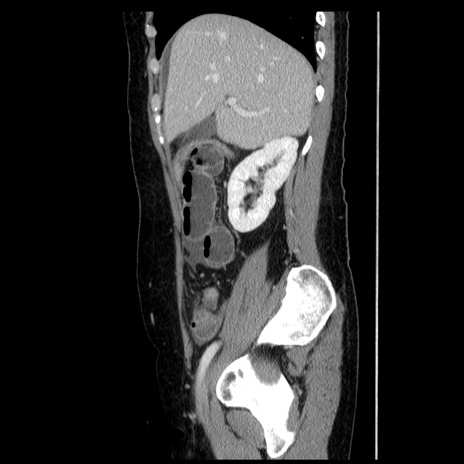

症例6(矢状断像)

【症例】50歳代女性

【主訴】下腹部痛

【現病歴】本日朝より下痢2回あり。 昼食を食べた後、嘔吐3回、下腹部痛認め、症状軽快せず、当院救急搬送。

最終食事:本日昼(生ものなし)。 昨日の夜、刺身を食ぺたとのこと。周囲に同様の症状の者なし。普段、排便は毎日あるとのこと。

【既往歴】卵巣癌術後(8年前に当院で卵巣摘出)

【身体所見】 意識清明、腹部:平坦、腸蠕動音→、やや硬、下腹部自発痛・圧痛あり、反跳痛あり、筋性防御なし。

【データ】WBC 16000、CRP 0.01

冠状断像